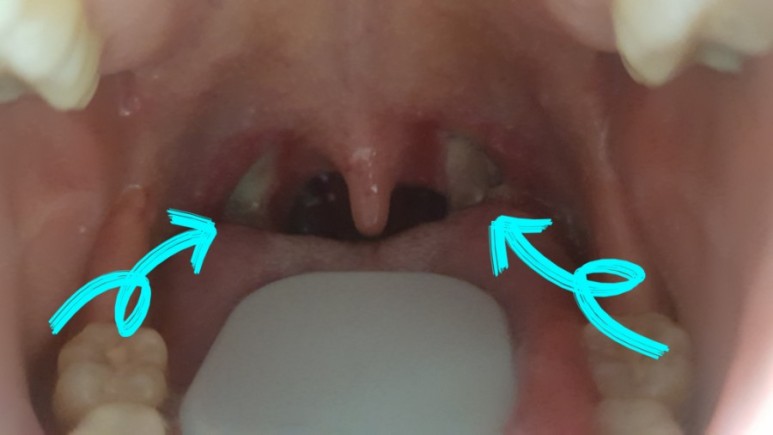

양쪽 구멍이 많이 떨어져 나가다가 보면 이 큰 게 언제 다 떨어져버리면 어떤 느낌일까 걱정했는데 음식 먹을 때마다 조금씩 떨어지는 것 같아서 그래서 원장님이 밥알이 좋은 자극제라고 했나봐